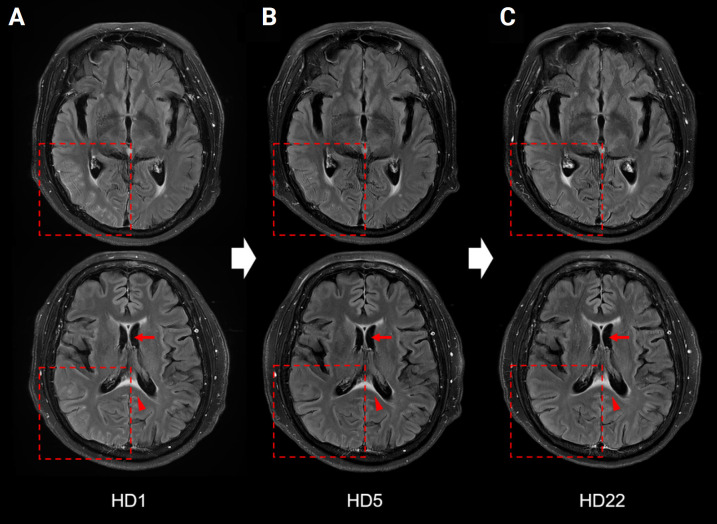

髓鞘少突胶质细胞糖蛋白抗体相关疾病(MOGAD)是一种自身免疫性疾病,临床表现多种多样,包括脊髓炎、脑膜炎、脑炎和视神经炎。MOGAD 很少表现为单侧大脑皮质脑炎(CCE),因此在这些病例中很难确诊。此外,MOGAD 常伴有其他自身免疫性疾病,如甲状腺疾病或炎症性肠病。在此,我们报告了一例抗髓鞘少突胶质细胞糖蛋白(MOG)抗体阳性的单侧CCE病例。此外,患者还伴有全身症状和神经系统症状,最终被诊断为溃疡性结肠炎(UC)。一名 60 岁的女性因急性头痛和发热入院。神经系统检查发现患者左侧同侧偏盲,间歇性视幻觉,左侧视野出现闪烁的红色圆点。脑磁共振成像显示右侧颞顶枕叶皮质局灶性高密度和强化。脑电图显示右枕叶皮层有局灶性癫痫发作。在服用抗癫痫药物后,患者的临床和影像学状况均有所改善。她的血清抗MOG抗体检测呈阳性,被诊断为抗MOG相关性单侧CCE。然而,患者的胃肠道症状仍然存在,因此进行了乙状结肠镜检查。患者被诊断为合并 UC。使用类固醇治疗 UC 后,胃肠道症状有所改善。据我们所知,这是韩国首例表现为单侧 CCE 的 MOGAD 病例。该病例强调了 MOGAD 的临床表型,以及评估 MOGAD 患者合并自身免疫性疾病的必要性。

Myelin oligodendrocyte glycoprotein antibody-associated disease (MOGAD) is an autoimmune disorder with diverse clinical manifestations including myelitis, meningitis, encephalitis, and optic neuritis. MOGAD rarely presents with unilateral cerebral cortical encephalitis (CCE), rendering the diagnosis difficult in these cases. Furthermore, MOGAD is frequently accompanied by other autoimmune diseases such as thyroid disease or inflammatory bowel disease. Herein, we report a case of unilateral CCE with positive anti-myelin oligodendrocyte glycoprotein (MOG) antibodies. In addition, our patient presented with systemic symptoms as well as neurologic symptoms and was finally diagnosed with ulcerative colitis (UC). A 60-year-old female was admitted to the hospital with an acute onset of headache and fever. Neurological examination revealed left-sided homonymous hemianopsia with intermittent visual hallucinations as flickering red-circular spots in the left visual field. Brain magnetic resonance imaging showed focal hyperintensities and enhancement in the right temporo-parieto-occipital cortex. Electroencephalography indicated a focal seizure in the right occipital cortex. After the administration of an antiepileptic drug, the patient showed clinical and radiological improvements. She tested positive for serum anti-MOG antibodies and was diagnosed with anti-MOG-associated unilateral CCE. However, the gastrointestinal symptoms persisted, thus, a sigmoidoscopy was performed. The patient was diagnosed with comorbid UC. Steroids were administered to treat the UC and the gastrointestinal symptoms improved. To the best of our knowledge, this is the first case of MOGAD presenting as a unilateral CCE in Korea. This case highlights the clinical phenotypes of MOGAD and the need to assess comorbid autoimmune diseases in patients with MOGAD.